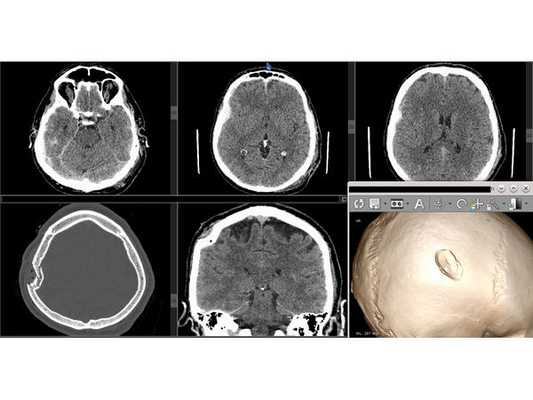

- Оскольчатый вдавленный перелом правой теменной кости.

- Острая пластинчатая субдуральная гематома в правой височно-теменной области.

- Открытый импрессионный (вдавленный) перелом правой теменной кости.

- Выполнен дугообразный разрез мягких тканей с захватом имеющейся раны.

- Скелетирована кость (надкостница отделена от кости). Гемостаз (остановка кровотечения) по ходу доступа. Визуализирован импрессионный перелом правой теменной кости.

- Краниотомом наложено фрезевое отверстие ниже вдавленного перелома и выпилен костный лоскут 5,0 х 6,0 см с захватом имеющегося импрессионного перелома. Костный лоскут временно удалён.

- Выполнена репозиция вдавленных фрагментов.

- Твёрдая мозговая оболочка (ТМО) вскрыта подковообразным разрезом. Путём аспирации (всасывания) и отмывания физиологическим раствором удалена пластинчатая субдуральная гематома малого объёма. ТМО ушита непрерывным швом с одновременным подшиванием по периметру трепанационного окна.

- Костный лоскут многократно обработан 3 % раствором перекиси водорода и уложен на место. Выполнен послойный шов раны. Кожные края ушиты непрерывным швом по Мультановскому.

На контрольной КТ головного мозга в послеоперационном периоде видна положительная динамика: состояние после краниотомии, репозиции вдавленных фрагментов теменной кости, удаления субдуральной гематомы, регресса дислокации срединных структур стабильное.